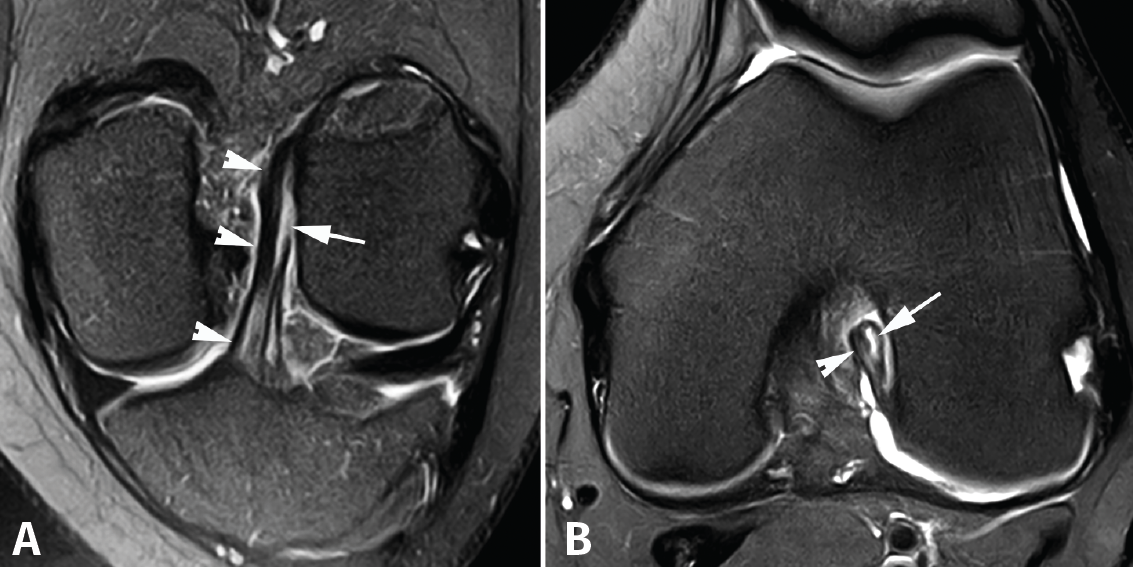

Los hallazgos de RM en las roturas parciales del LCA consisten en un aumento de la señal intrasustancial, defectos focales, distorsión y atenuación de fibras o una orientación anormal del ligamento(1,16)(Figuras 4 y 5). El diagnóstico es más sencillo en fase aguda, por la presencia de signos secundarios con edema y derrame articular. La principal dificultad diagnóstica con RM en la fase aguda consiste en diferenciar roturas parciales de alto grado de completas(1,16).

Figura 5. Rotura parcial del fascículo posterolateral (PL) del ligamento cruzado anterior (LCA). Corte oblicuo coronal (A) y axial (B) de resonancia magnética (RM) potenciados en densidad protónica con supresión grasa que muestran una rotura completa proximal del fascículo PL (flechas). Fascículo anteromedial normal (cabezas de flecha).